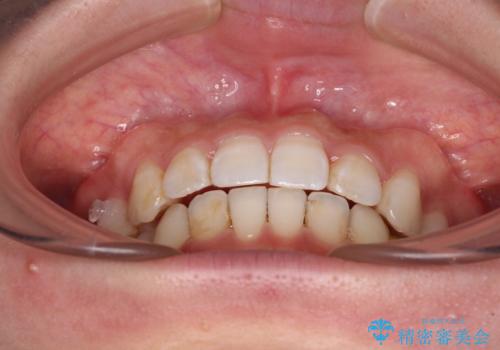

- 前歯のデコボコと深い咬み込みを気にして来院された患者様です。

インビザラインを用いて、前歯の叢生を解消するとともに、深い咬み合わせ(ディープバイト)を改善していくこととしました。

奥歯を後方に直立させることで深い咬み合わせを改善を図り、隠れていた下顎前歯が見えるほどになりました。